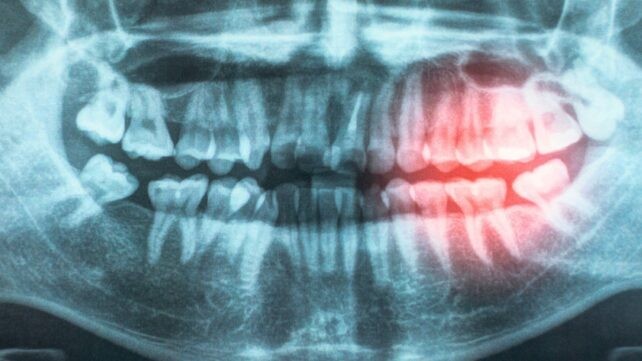

Una revisión de la American Heart Association Cardiovascular Disease Prevention Committee refuerza la idea de que mantener nuestras encías sanas ayuda a proteger contra la enfermedad cardíaca. Basada en una década de literatura que incluye investigaciones genéticas, ensayos clínicos y pruebas de laboratorio, su informe actualiza su declaración científica de 2012, proporcionando aún más evidencia de que los problemas cardíacos desencadenados por la aterosclerosis (enfermedad cardiovascular aterosclerótica, o ASCVD) están estrechamente asociados con la enfermedad periodontal. Como parte de la revisión, los investigadores exploraron posibles razones de la asociación, incluida la posibilidad de que las bacterias entren al cuerpo a través de encías expuestas y dañadas, contribuyendo a la inflamación crónica. Relacionado: Estudio vincula la enfermedad de las encías con daño de la sustancia blanca en el cerebro. "Tu boca y tu corazón están conectados," dice el cardiólogo pediátrico Andrew Tran. "La enfermedad de las encías y la mala higiene bucal pueden permitir que las bacterias entren en el torrente sanguíneo, causando inflamación que puede dañar los vasos sanguíneos y aumentar el riesgo de enfermedad cardíaca." Uno de los mayores desafíos para quienes estudian este vínculo es que muchos factores de riesgo —desde el tabaquismo hasta el envejecimiento y la obesidad— aumentan las probabilidades de tanto la enfermedad de las encías como la ASCVD. Sin embargo, nueva evidencia ha seguido emergiendo, lo que sugiere que hay una asociación independiente entre las dos condiciones. ASCVD continúa siendo la principal causa de muerte a nivel mundial, y si mejorar la higiene bucal podría ser una de las formas de evitar que ocurra, vale la pena investigarlo. Algunos de los estudios analizados incluyeron detalles sobre sujetos que remontan a la infancia, encontrando que cuidar tus dientes a una edad temprana podría reducir el riesgo de problemas cardíacos más adelante en la vida. "Existe evidencia sólida de que tratar la enfermedad periodontal mejora las medidas de resultado intermedias, como la presión arterial, el nivel de lipoproteína de alta densidad y los marcadores inflamatorios," escriben los investigadores en su artículo publicado. "Este es un hallazgo importante porque estas medidas de resultado son conocidas por aumentar el riesgo cardiovascular futuro y proporcionan un posible vínculo entre la enfermedad periodontal y ASCVD." El panel detrás de la nueva investigación solicita más estudios detallados y a largo plazo para ampliar la investigación existente sobre la enfermedad cardíaca y la salud de las encías, incluyendo si los tratamientos para la enfermedad periodontal establecida reducen la probabilidad de ASCVD — otro dato útil para sopesar la causalidad. Por supuesto, también hay muchos otros beneficios de mantener una buena higiene bucal, incluyendo no tener que acudir al dentista para empastes. Investigaciones anteriores también han vinculado una boca limpia y saludable con condiciones como la diabetes e incluso el cáncer. Si eso te anima a cepillarte los dientes antes de acostarte esta noche, piensa en todos los efectos beneficiosos en cascada que podría estar teniendo sobre el resto de tu salud, incluida la reducción de la inflamación y la prevención de la enfermedad de las encías que podría, en última instancia, conducir a ASCVD. "Cepillarse, usar hilo dental y chequeos dentales regulares no se trata solo de una sonrisa saludable – son una parte importante de proteger tu corazón," dice Tran. La investigación ha sido publicada en Circulation.